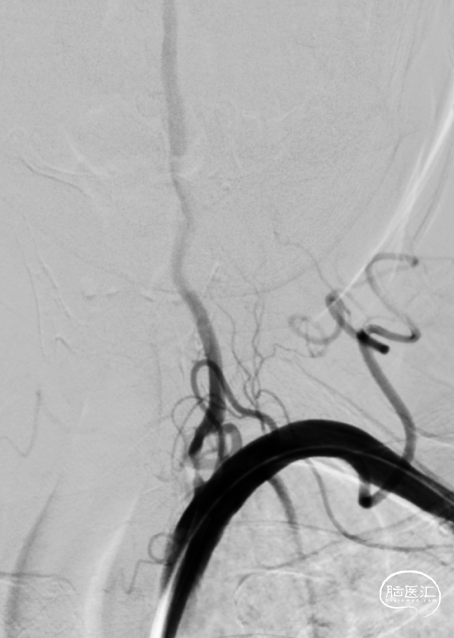

全脑血管造影DSA:双侧椎动脉起始段狭窄。远端供血不足。

患者双侧椎动脉均狭窄,左侧重度狭窄。左侧椎动脉充盈延迟、血流瘀滞,为闭塞前表现。所以权衡双侧椎动脉狭窄血管成型术的指征,优先处理左侧椎动脉起始段狭窄。为预防急性后循环缺血性卒中,在家属知情同意前提下行支架成形术。

8F导引导管到达锁骨下动脉。

微导丝通过椎动脉起始处狭窄段,到达椎动脉V3段。